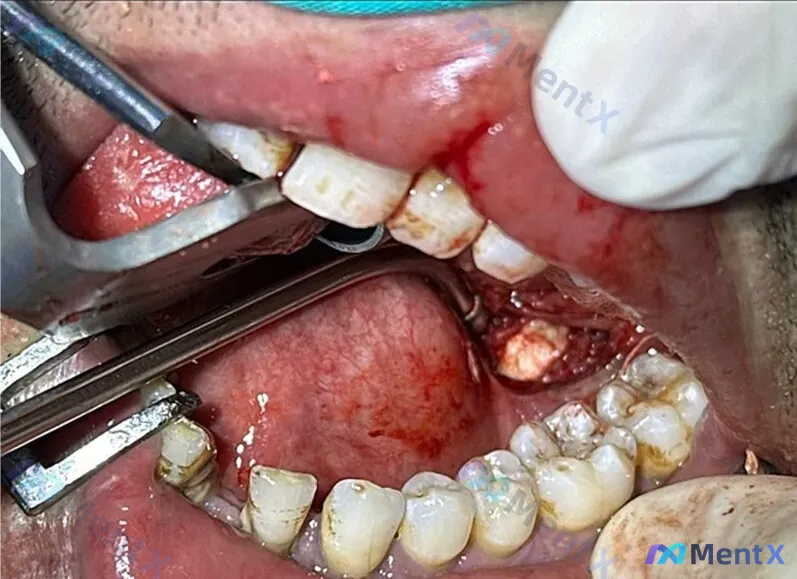

术野在下颌右侧后牙区,翻瓣后可见深部有一块不规则的阻射影(类似骨组织的白色高密度影),周围有血性液体和软组织残留,邻牙还有牙结石和色素沉着。

从影像画面看,首先会考虑是残根?骨内病灶?还是别的什么?

📋答案:术中取出物为下颌下腺结石,深部不规则阻射影符合游离/异位或骨内涎石病表现,需注意与牙源性骨病变鉴别。